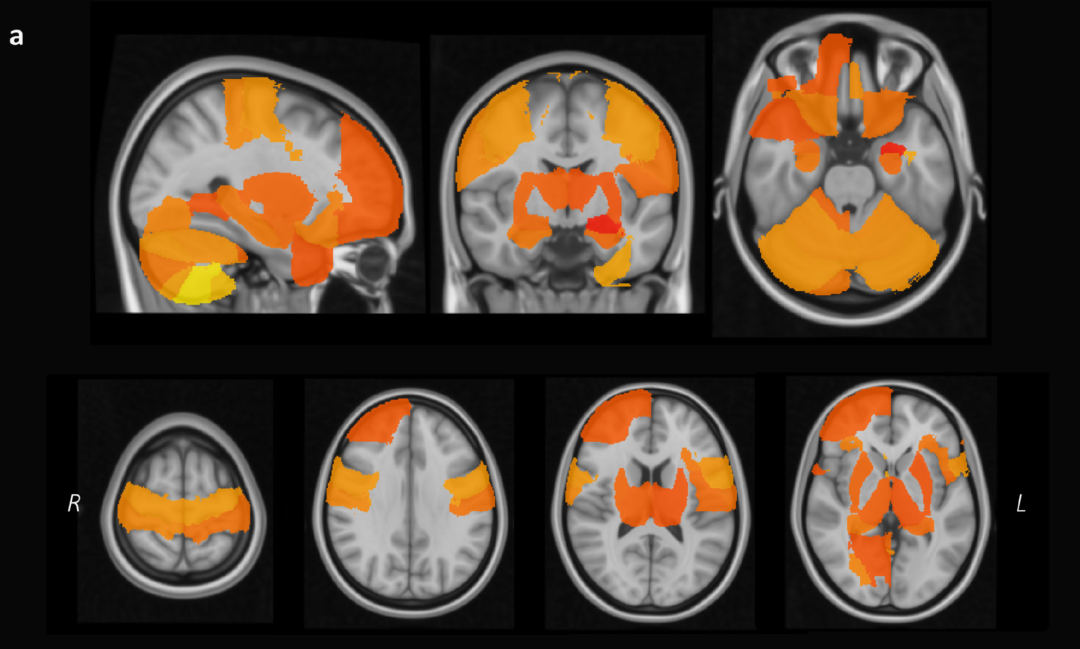

更为深刻的是,与每晚睡眠充足 6~8 小时的人相比,睡眠时间少于 6 小时的人,大脑体积更小,比如右侧伏核体积减小 2.0%至右前极体积减小 0.5%。

图片来自参考文献[9]:睡眠 6~8 小时的人大脑体积更大